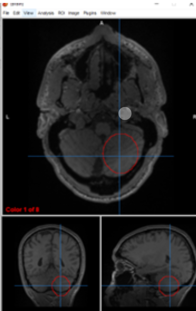

right inferior colliculus

left hearing

medial geniculate nucleus

transferring sound information from inferior colliculus to primary auditory cortex